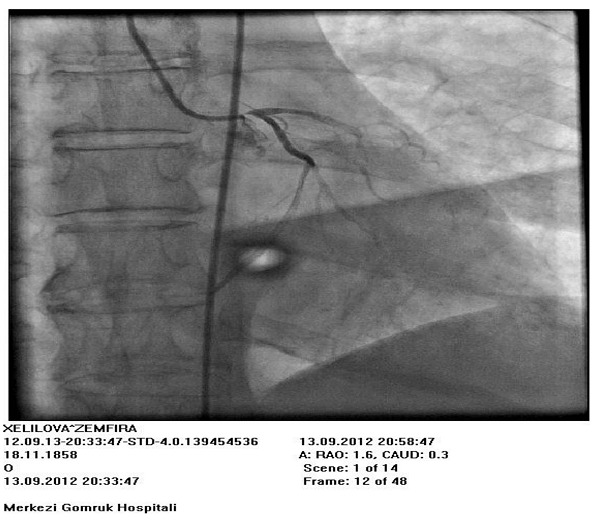

Kardiogen şokla ağırlaşan ST elevasiyasız miokard infarktı keçirən xəstənin sol ana koronar arteriyasının ostiumuna təcili perkutan müdaxilə Dərc edilib: Cild 1, Nömrə 1, 2012 / Nəşr tarixi: 10.04.2012

Ülvi Mirzəyev